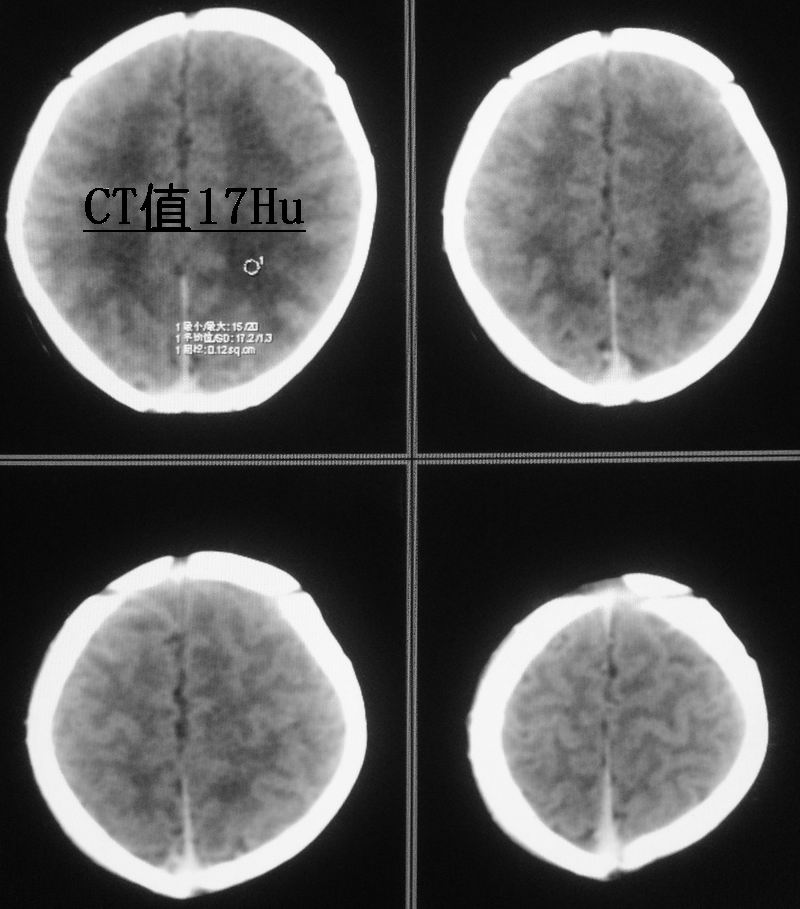

新生儿,男性,5天,出生时有短暂窒息史。现一般情况较好,面色红润,无明显发绀,原始反射尚可。经治医生和家属均不放心,要求ct。

小孩脑实质内可见多发对称性低密度灶,ct值17~20hu,我也考虑有缺血缺氧性脑病存在。

可问题是患儿虽有短暂的窒息史,却并没有明显的临床症状,实在不好解释。这就牵涉到新生儿的脑的正常ct值的问题,为此专门查了一点资料:

曹连义等曾报道足月新生儿脑组织ct值明显低于儿童及成人,建议新生儿期ct正常值为18~40 hu,低于18 hu为低密度[1-2]。对不同胎龄新生儿脑组织ct值正常范围及平均值国内未见报道。本研究显示即使新生儿期若胎龄不同,各部位脑组织(小脑、脑干、基底节、丘脑、白质、灰质)ct值均明显不同,胎龄越小,脑ct值越低,与国外学者报道一致[3]。其原因:(1)与脑组织含水量有关,胎龄越小,脑组织含水量越多;(2)胎龄越小,神经细胞髓鞘形成越不完全。故足月新生儿脑组织ct值正常范围不适用于早产儿,不同胎龄新生儿应有不同的正常值,这样才不致于将早产儿正常发育过程中的脑组织低密度误诊为脑水肿、缺氧缺血性脑病。

新生儿缺血缺氧性脑病的诊断应紧密结合临床.片上所见之对称性稍低密度影,很可能是窗宽窗位未调好,本人在工作中也遇到过这种情况,调节好窗宽窗位可避免误诊.新生儿及儿量脑细胞水份含量多于成人,因此脑实质密度更低,脑沟亦较浅.

新生儿缺血缺氧性脑病的诊断应紧密结合临床;脑白质ct低于18hu考虑缺血缺氧改变。